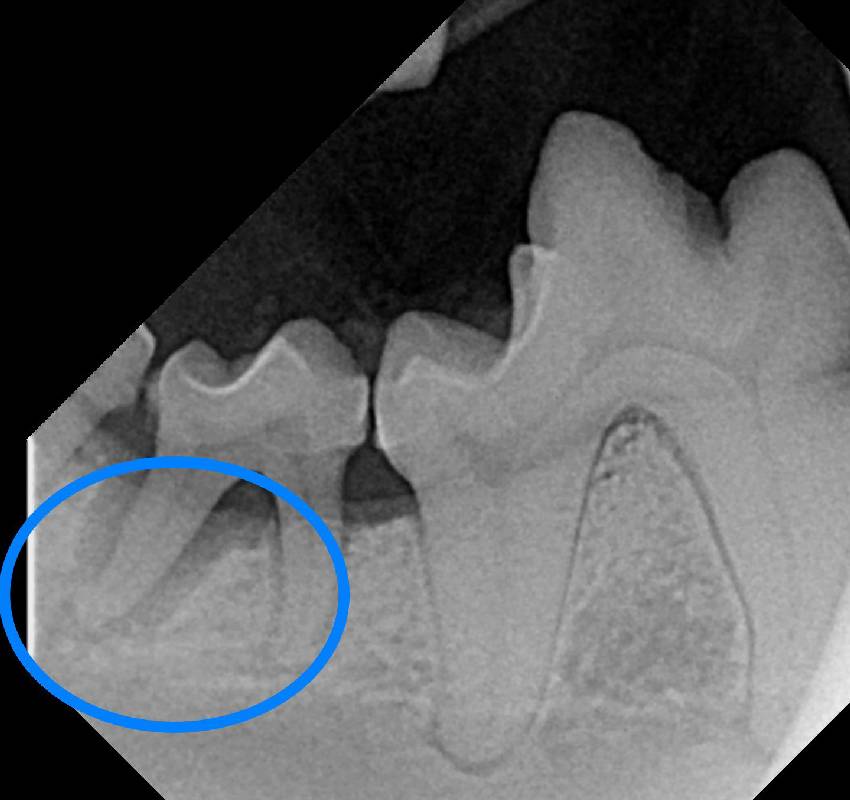

This very unique form of imaging is so near and dear to our hearts that we gave it its own section apart from our dentistry page . While a complete oral exam and health assessment is critical for every patient receiving dental work, it simply is not possible without the use of dental x-rays. The small sensor plate and handheld generator allow us to look at the bone and root structures of the teeth in a way that simply is not possible by visually examining the mouth or even with normal digital radiography. These small, more focused x-rays help us look at each tooth individually and how it is attached to the surrounding bone. In fact, roughly 60% of the tooth surface actually lives below the gum line and would be completely invisible to the veterinarian simply by looking in the mouth to evaluate the teeth. Think of teeth a lot like how you would think of an iceburg-it’s what is lurking below the surface that is worrisome. With dental x-rays, we can observe:

• Root fractures

• Abscesses (pockets of infection) in the tooth roots or bone

• Resorptive lesions

• Pulp chamber (where the tooth vessel and nerve lives) infection or inflammation

• Jaw Tumors or fractures

• Foreign material in the bone or below the gums (yes, we have found metal foreign bodies in the mouth this way!)

• Bone loss around the tooth roots.

Dental X-rays